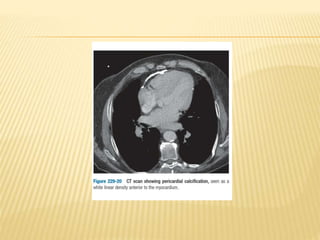

 Important clinical applications

 Pericardial calcification

CT SCAN  Fastsimple, noninvasive technique that provide images of myocardium and great vessels with excellent spatial resolution and good soft tissue contrast.  Important clinical applications  Pericardial calcification  Cardiac masses, particularly those containing fat or calcium.  Suspected arrhythmogenic right ventricular dysplasia